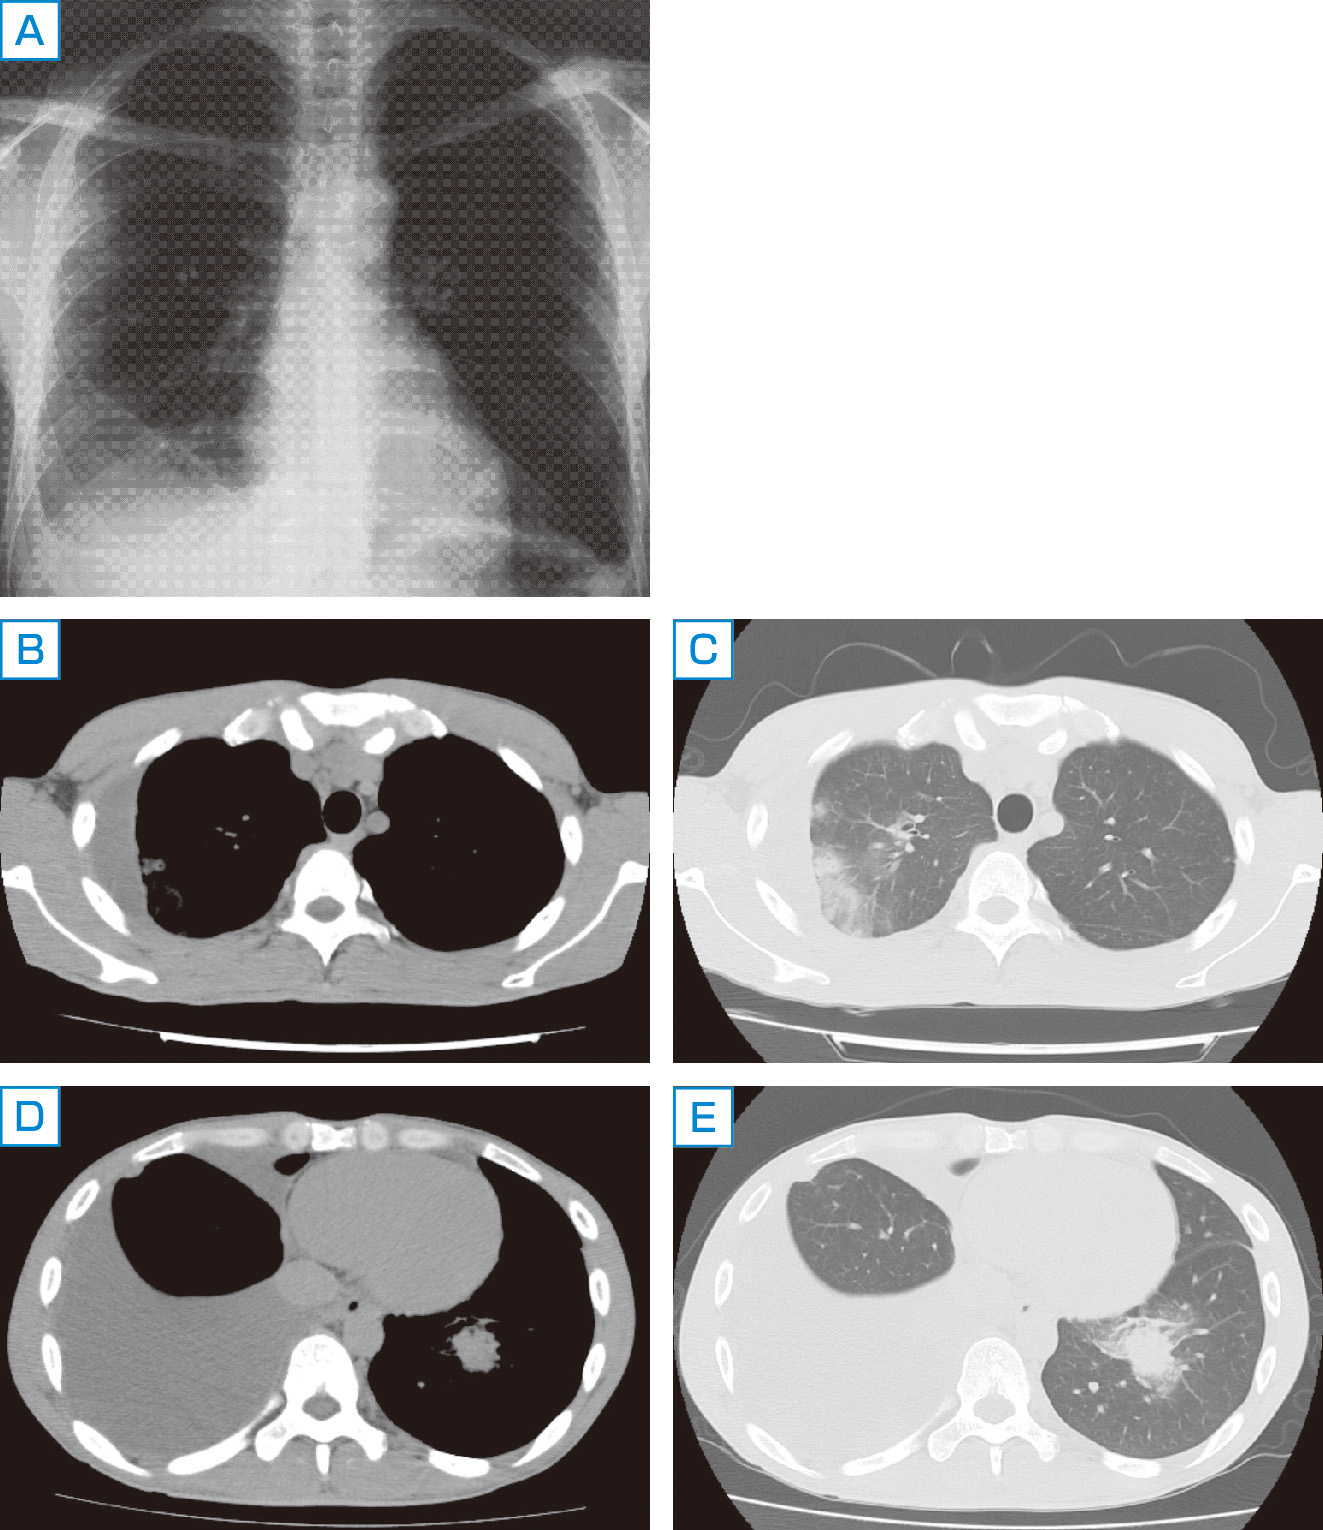

Yahoo!オークション - n 古い教科書 徒然草・枕草子・源氏物語, 朝倉書店『内科学』(第12版)デジタル付録,

朝倉書店『内科学』(第12版)デジタル付録, zaa-598 日本人体解剖学 第2巻 内蔵学・感覚器学 改訂11版 金子,